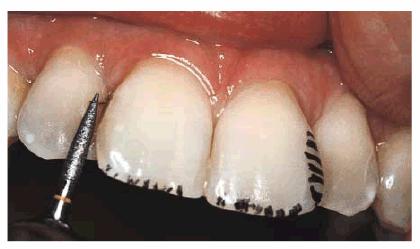

Esthetic Contouring and Porcelain Laminates to Eliminate Crowding

PROBLEM: This 58-year-old housewife was concerned about her eroded,

crowded, and stained front teeth (Figures 24-5A, and 24-5B). Measurement with a dental dial

caliper helped to accurately determine available space for reproportioning tooth

size (Figure 24-5C). Although orthodontics was

mentioned as a first step to an ideal solution, the patient preferred to accept

a compromise treatment of porcelain laminates and cosmetic contouring. Although

crowding was less of a concern to the patient (Figures 24-5D, and 24-5E), she nevertheless decided to have

straighter-looking teeth through a compromise treatment of porcelain laminates

that would also esthetically correct the erosion and discoloration.

Figure

24-5C: Each tooth and the available space for the laminated teeth are measured

with Dental Dial Calipers (Masel Enterprises,